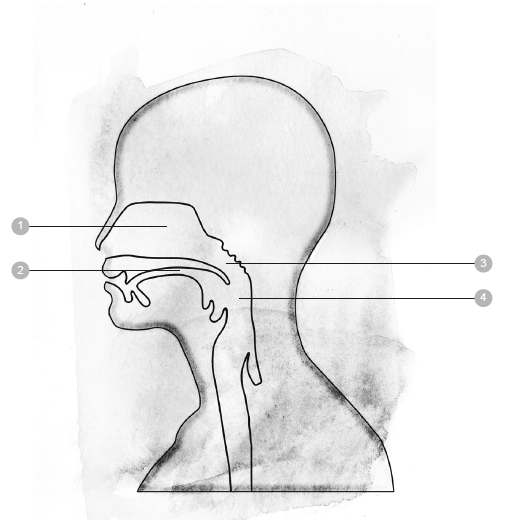

1 鼻子 6 肋间肌 11 气管

2 口 7 横膈膜 12 肺

3 会厌 8 鼻腔 13 支气管

4 胸膜 9 咽头(喉咙) 14 肺泡

5 肋骨 10 喉头

✘误解二:鼻腔里面的通道是朝上的

鼻腔里面的通道到底是什么样的?先来做做下面这个练习,有助于你建立正确的认知。

觉察练习6的解答

肺脏在身体内的实际大小和位置

觉察练习7

把下面的图片影印下来,或是照着这张图片画出头部的轮廓。

根据你的想法,空气经过鼻腔通道,而后进入气管的路线是怎么走的呢?

请在下面的图上画一道箭头,把你所认为的路线标示出来。

人们普遍认为空气进入鼻腔的路线是朝上的,事实却不是如此。其实,空气是循着水平的方向前进。现在,试试下面的练习:

觉察练习8

1. 一边想像空气往上进入你的鼻腔,一边呼吸。这个动作说来很简单,实际去做的时候,你有没有觉得必须费力而感到紧绷呢?

2. 这回吸气时,想像空气经由水平路线进入你的鼻腔。有没有觉得轻松许多了呢?这种吸气的方法不会造成任何紧绷感。

翻到下一页的图片,你便会看到,鼻腔的通道大部分是水平的。

✘误解三:憋气可以强化呼吸肌

憋气是很常见的呼吸练习,这个方法源自于古代的瑜珈传统,修行人把憋气视为调和身体的步骤之一。时至今日,从游泳健将到歌手,许多人的练习项目也包括憋气在内,他们误以为这样做可以改善呼吸方式,或是增强呼吸肌。事实上,憋气会使呼吸系统变得衰弱,反而达不到强化的效果。每个人偶尔都会憋气,那是面对压力时的自然反应,看看表演者、演说者在准备过程或上台前的紧张模样,便可以明白这一点。

察觉练习8的解答

请注意看清楚,空气所走的通道,有一大段是水平的。